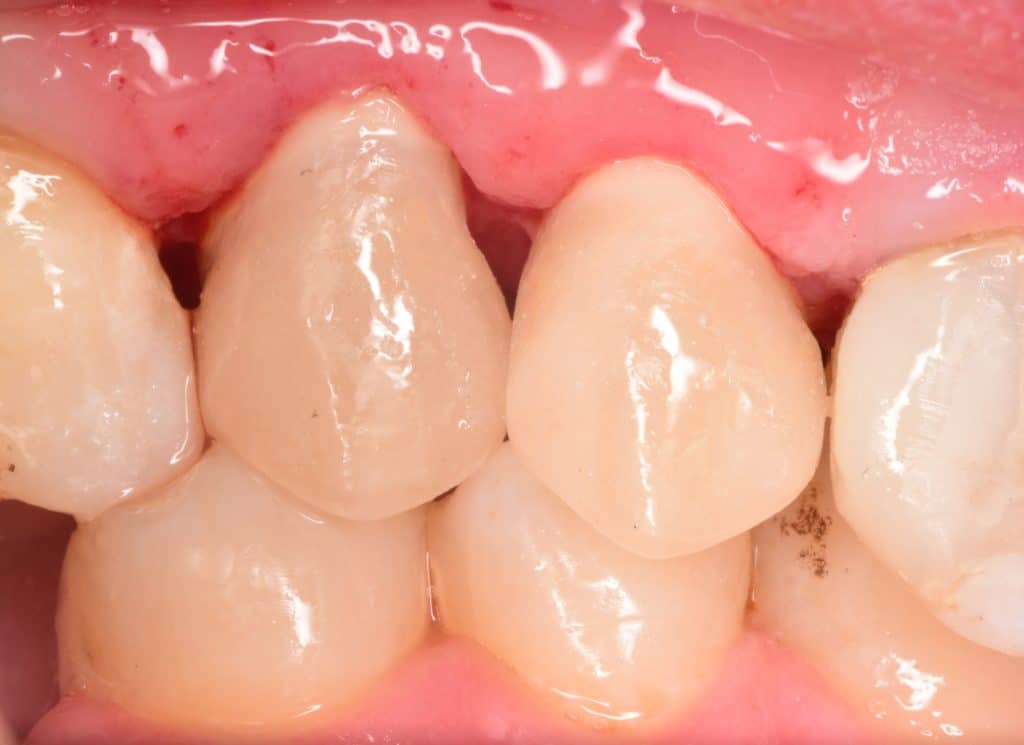

2 weeks later, healing of the soft tissue 💙

Buccal view, look to the healing